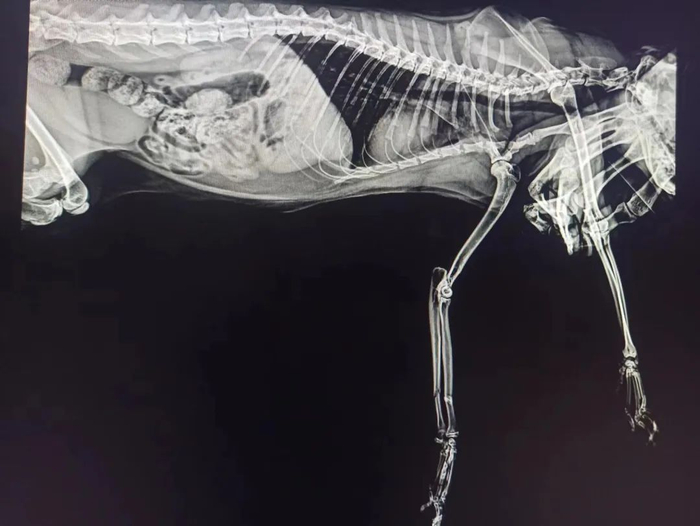

4月15号,接了两个急诊,是小动物跳楼的。大多数猫咪好奇心重,向往自由,如果阳台没封或忘记关窗,猫咪的活动空间就可能扩展到窗边风险区。有些纯粹是脚滑不小心掉下楼,有些却是扑鸟扑虫时计算失误。未绝育的猫在发情期更向往外面的世界,同时疫情期间主人在家时间增多,也让一部分不喜欢被撸的猫躲到阳台上。这两例高楼坠落的,都有内伤出血和骨折。还好送医及时,现在都出院了。

摔裂上颚的小猫。

摔断前肢的小猫。